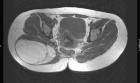

J.R. - 45 year old female with large buttock mass

Zoom image: Radiological image Radiological image.